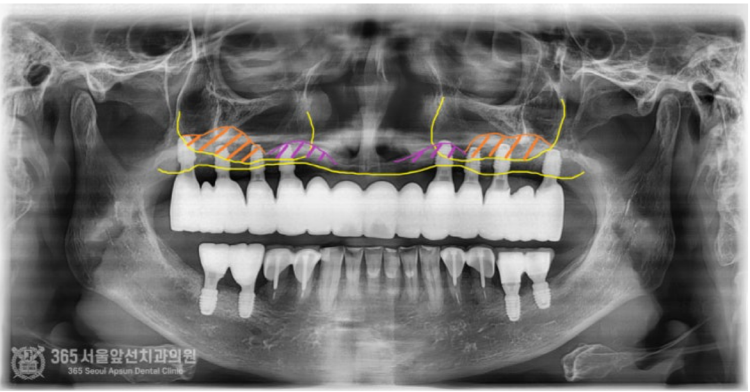

촬영일시: 2024.06.07. 처음 오셨을때 엑스레이 사진입니다. 윗턱과 아래턱 모두 뼈가 매우 적은편입니다. 특히 윗턱의 앞니쪽은 뼈가 고작 3mm밖에 존재하지 않았습니다. 매우 난증례에 해당한다고 볼 수 있겠습니다. 앞니 부위 뼈가 매우 부족하고(3mm) 어금니쪽도 전체적으로 뼈가 매우 적었습니다. 앞니와 어금니의 부족한 뼈를 만들어내면서 임플란트 식립을 계획했습니다. 통상적으로 윗턱에서 뼈가 부족할때 사용하는 수술방법으로 상악동거상술이라는 잘 알려진 술식이있는데요. 상기 환자분의 경우, 앞니쪽까지도 뼈가 부족했기에 코로 접근해서 부족한 뼈를 만들어 내는 비강거상술까지 동반하여 임플란트 수술을 진행했습니다. 촬영일시: 2024.08.10. 좌우측 상악동 거상과 비강거상을 동반하여 윗턱에 임플란트 8개를 식립했습니다. 지금까지 만나뵈었던 많은 환자분들 중 뼈의 상태가 매우 안좋은 편에 속하셨으며 매우 난해한 증례였습니다. 그렇지만 수술은 성공적으로 잘 마무리되었습니다. 위아래 전체 임플란트를 식립한 후 엑스레이 사진입니다. 임플란트가 가지런히 잘 배열되어있습니다 ㅎㅎ 지르코니아라는 재료를 사용하여 치아색상으로 단단하게 보철물도 제작했습니다. 촬영일시: 2024.12.29. 최종적으로 마무리된 엑스레이 사진입니다. 촬영일시: 2024.12.29. -노란색: 원래 환자분의 윗턱뼈 -주황색: 상악동거상술을 통해 만들어진 뼈 -보라색: 비강거상술을 통해 만들어진 뼈 최종적으로 치료가 완료된 후 구강내 사진입니다.